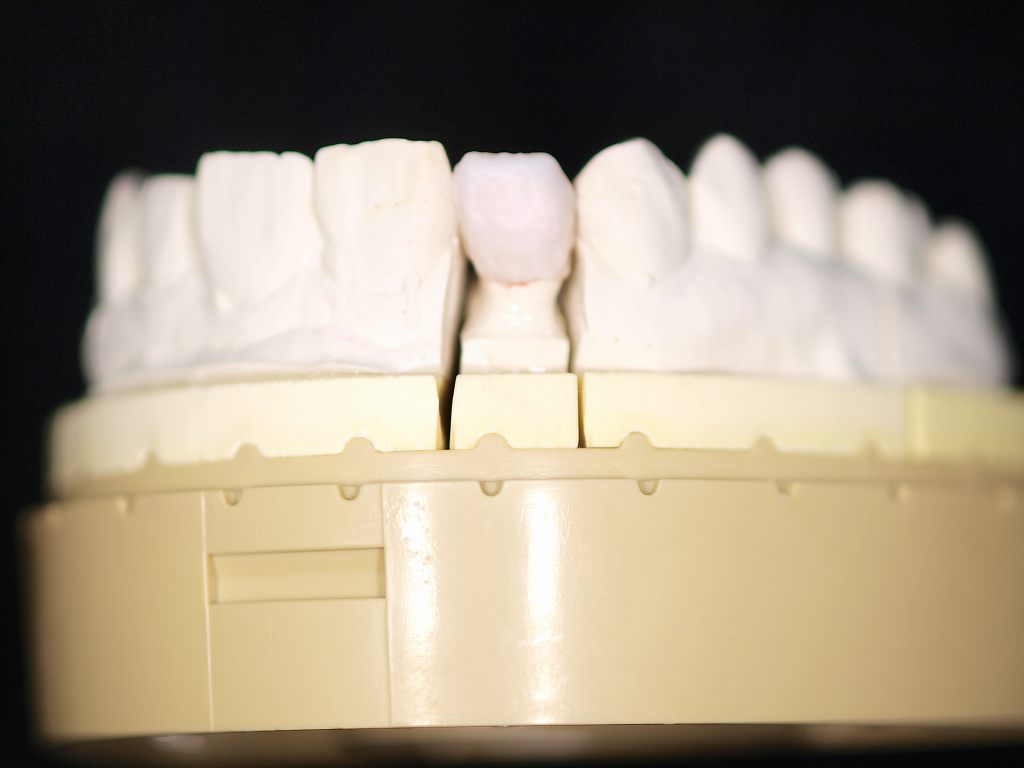

ジルコニアクラウンの作成の様子になります。 前歯部の作成と臼歯部の作成の両方をご紹介します。 前歯部はポーセレンの築造割合が高くなりますが、臼歯部は逆にジルコニアフレームにて咬合させるようになります。 前歯部のポーセレンの築造にはベテランの技術を要します。|お知らせ |広島市安佐南区の歯科医院

ジルコニアクラウンの作成の様子になります。 前歯部の作成と臼歯部の作成の両方をご紹介します。 前歯部はポーセレンの築造割合が高くなりますが、臼歯部は逆にジルコニアフレームにて咬合させるようになります。 前歯部のポーセレンの築造にはベテランの技術を要します。

ジルコニアクラウンの作成の様子になります。 前歯部の作成と臼歯部の作成の両方をご紹介します。 前歯部はポーセレンの築造割合が高くなりますが、臼歯部は逆にジルコニアフレームにて咬合させるようになります。 前歯部のポーセレンの築造にはベテランの技術を要します。